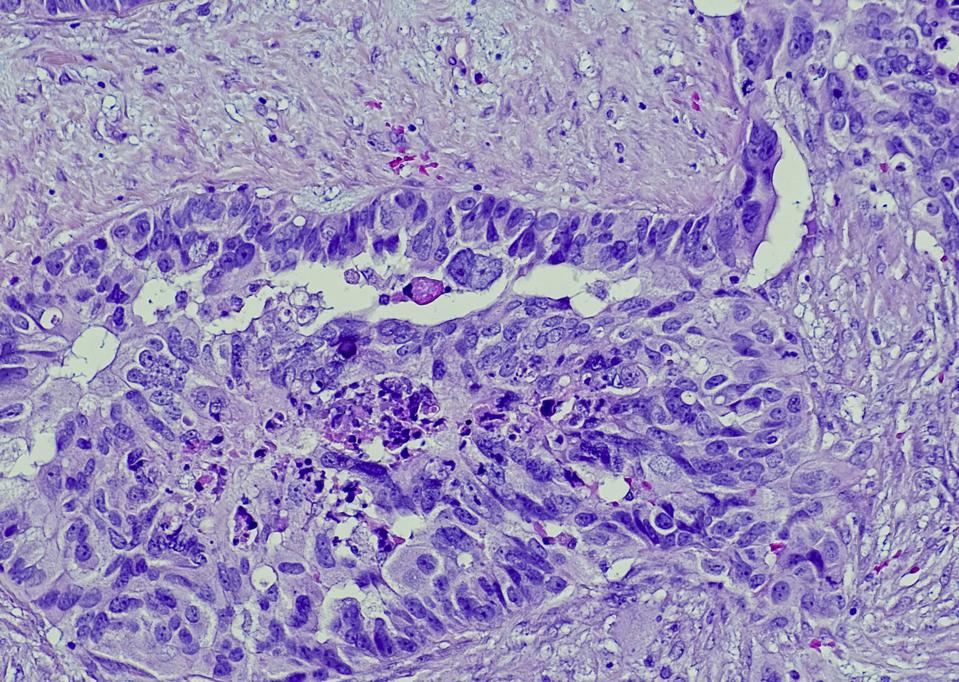

Serous carcinoma is the most common type of ovarian cancer, accounting for approximately 75% of epithelial ovarian cancers.

GETTY